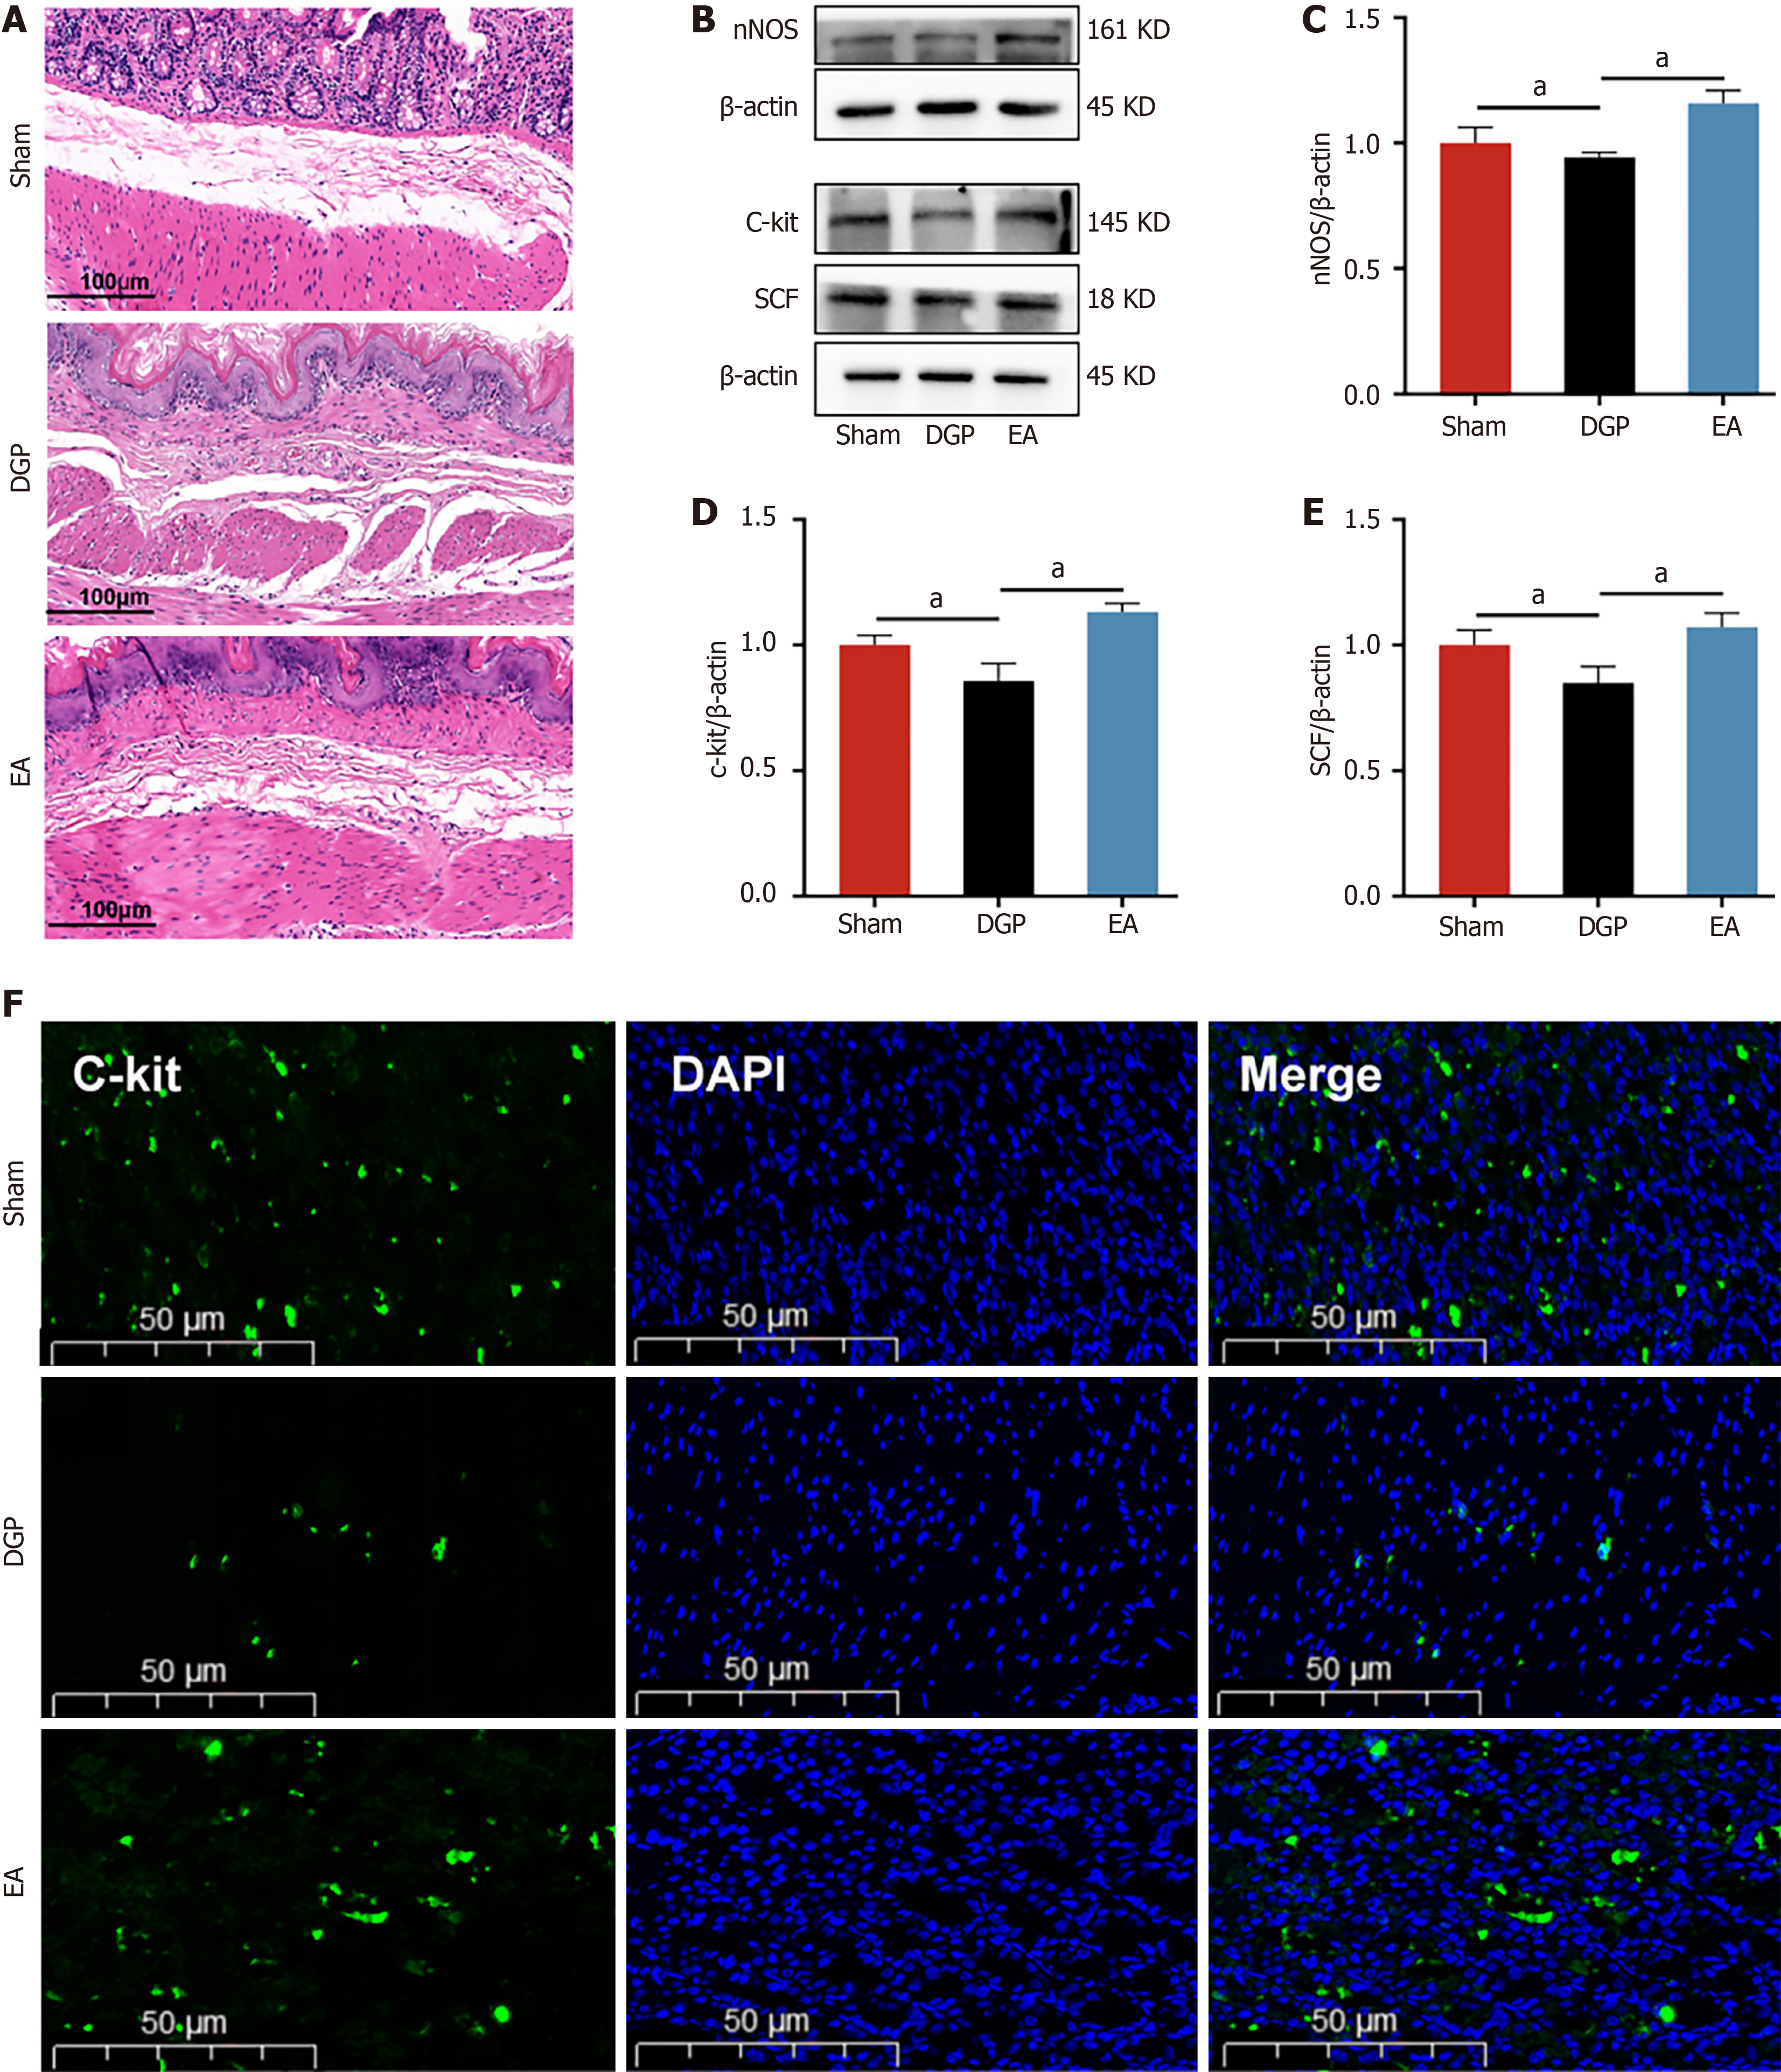

Having established the regulatory effects of EA on gastric emptying, the subsequent focus was on gastric smooth muscle dynamics, which are the primary driver of gastric contractility. Histopathological evaluation via HE staining (Figure 2A) revealed distinct morphological profiles across the experimental groups. Sham controls displayed preserved gastric architecture, with intact mucosal layers and orderly smooth muscle arrangement. In contrast, DGP rats exhibited marked mucosal degeneration, characterized by glandular atrophy, inflammatory infiltrates, submucosal fibrosis, and disrupted smooth muscle organization. The administration of EA significantly mitigated these pathological manifestations, as evidenced by the restoration of glandular density, the attenuation of inflammatory infiltration, and the enhancement of smooth muscle alignment. In order to investigate the molecular mechanisms underlying these morphological improvements, a study was conducted on the key regulators of smooth muscle function. Western blot analysis demon

The vagus nerve is the principal neural regulator of gastrointestinal motility. In order to elucidate its role in EA-mediated improvements, a comprehensive analysis was conducted on key vagal targets in gastric tissues. The results of the immunoblot analysis revealed that EA induced upregulation of the cholinergic markers ChAT and α7nAchR in comparison with DGP controls (P < 0.05, Figure 3A-C). Furthermore, immunofluorescence co-localization analysis demonstrated parallel restoration of C-kit +/ChAT + expression patterns, with EA-treated rats showing distribution characteristics comparable to the Sham group (Figure 3D). This suggests that the vagus nerve target ChAT may be involved in the regulatory effect of EA on ICC. Assessment of gastrointestinal peptides further revealed characteristic alterations. Compared with the Sham group, DGP rats exhibited significant suppression of stimulatory mediators (Gas and MLT), accompanied by a concomitant paradoxical elevation in inhibitory VIP levels (P < 0.05). However, the EA intervention led to the normalization of these peptide profiles, with a significant increase in Gas and MLT levels (P < 0.05) and a reduction in VIP levels (P < 0.05) (Figure 3E-G). The EA intervention appears to have restored gastric motility in DGP rats by coordinating the activation of the vagal cholinergic pathway to regulate ICC cells and rebalance neuroendocrine signals.